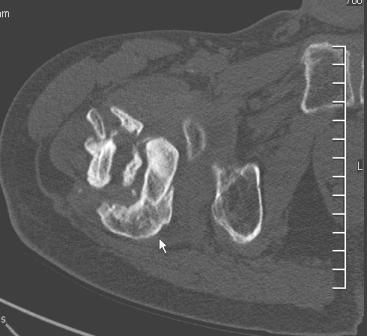

[Ortho] Сросшийся со смещением чрез-подвертельный перелом

Больной Н. 44 года травма 1,5 года назад июнь 2008 года чрез-под вертельный  перелом правого бедра. Во время лечения у больного развился алк делирий,  проводилось консертативное лечение перелома.

На КТ перелом сросся за счет костной мозоли.